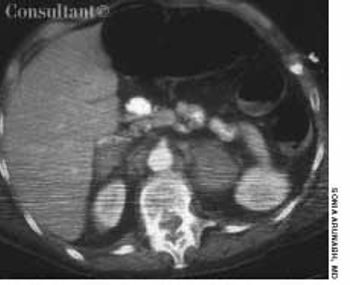

For 2 years, a 55-year-old woman's abdomen gradually enlarged; the pace of this growth had accelerated during the last 6 months. The patient, who had not seen a physician in 10 years, denied abdominal pain, nausea, vomiting, constipation, diarrhea, or any change in bowel habits. She had no shortness of breath or weakness. The patient reported no significant medical history, had no allergies, and took no medications. Her mother had died of ovarian cancer.